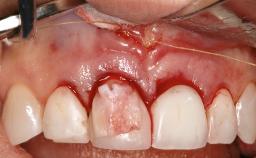

A 37-year-old male patient was referred to the Department of Periodontology at the University of Bern, Switzerland, by a private dentist. Tooth 21 had been lost due to trauma and had been replaced with an implant and a cemented single crown. The tapered-effect tissue-level implant had a diameter of 4.1 mm, a length of 12 mm, and a sandblasted and acid-etched (SLA) surface (Straumann Dental lmplant System; Institut Straumann AG, Basel, Switzerland). The metal-ceramic crown had been cemented permanently, leaving a submucosal gap between the implant shoulder and the crown margin. Absence of marginal bone loss apical to the polished transmucosal neck of the implant could be observed .